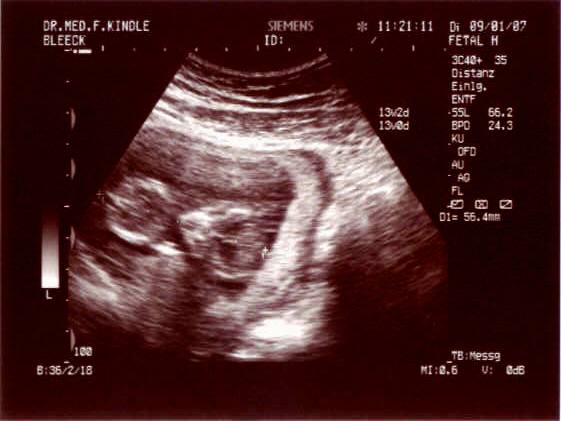

@all wollt ihr US Bilder sehen???

Das erste ist bei 10+0 entstanden und das zweite bei 12+5 wo die Nackenfalte gemessen wurde.